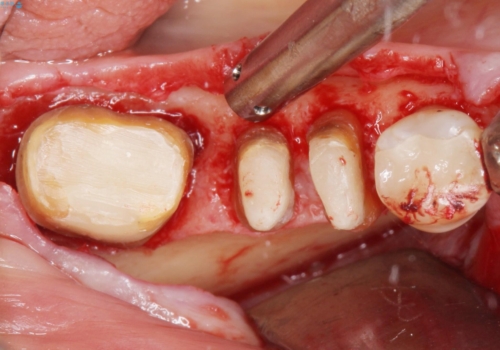

「抜歯したくない、インプラントは嫌」という患者様のご希望とご年齢を考慮し、可及的な骨外科処置や根分割術によりできるだけ今ある歯を残す治療方針をたてました。

- 外科手術のため、術後に痛みや腫れ、違和感を伴います

- 歯周組織再生治療は患者様の状態によって術後の経過が異なります(見た目が改善しない場合もあります)